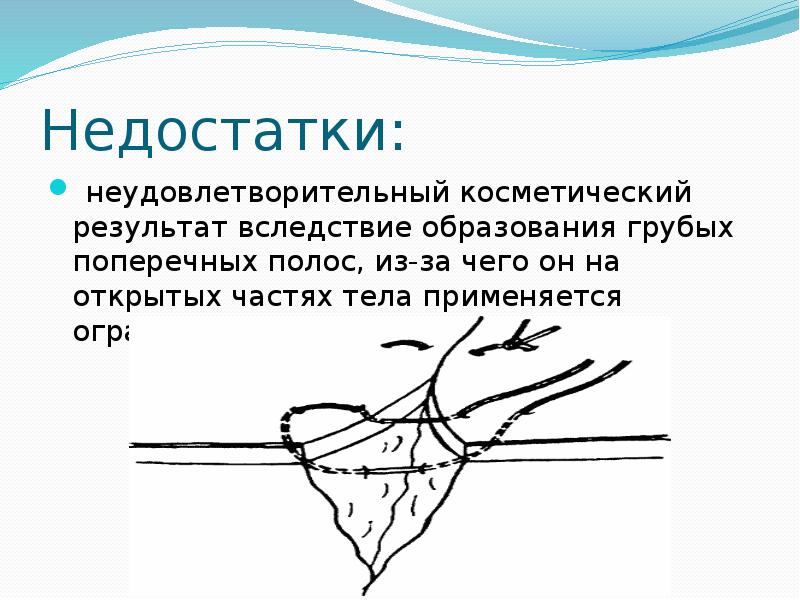

- 33. Недостатки: неудовлетворительный косметический результат вследствие образования грубых поперечных полос, из-за чего